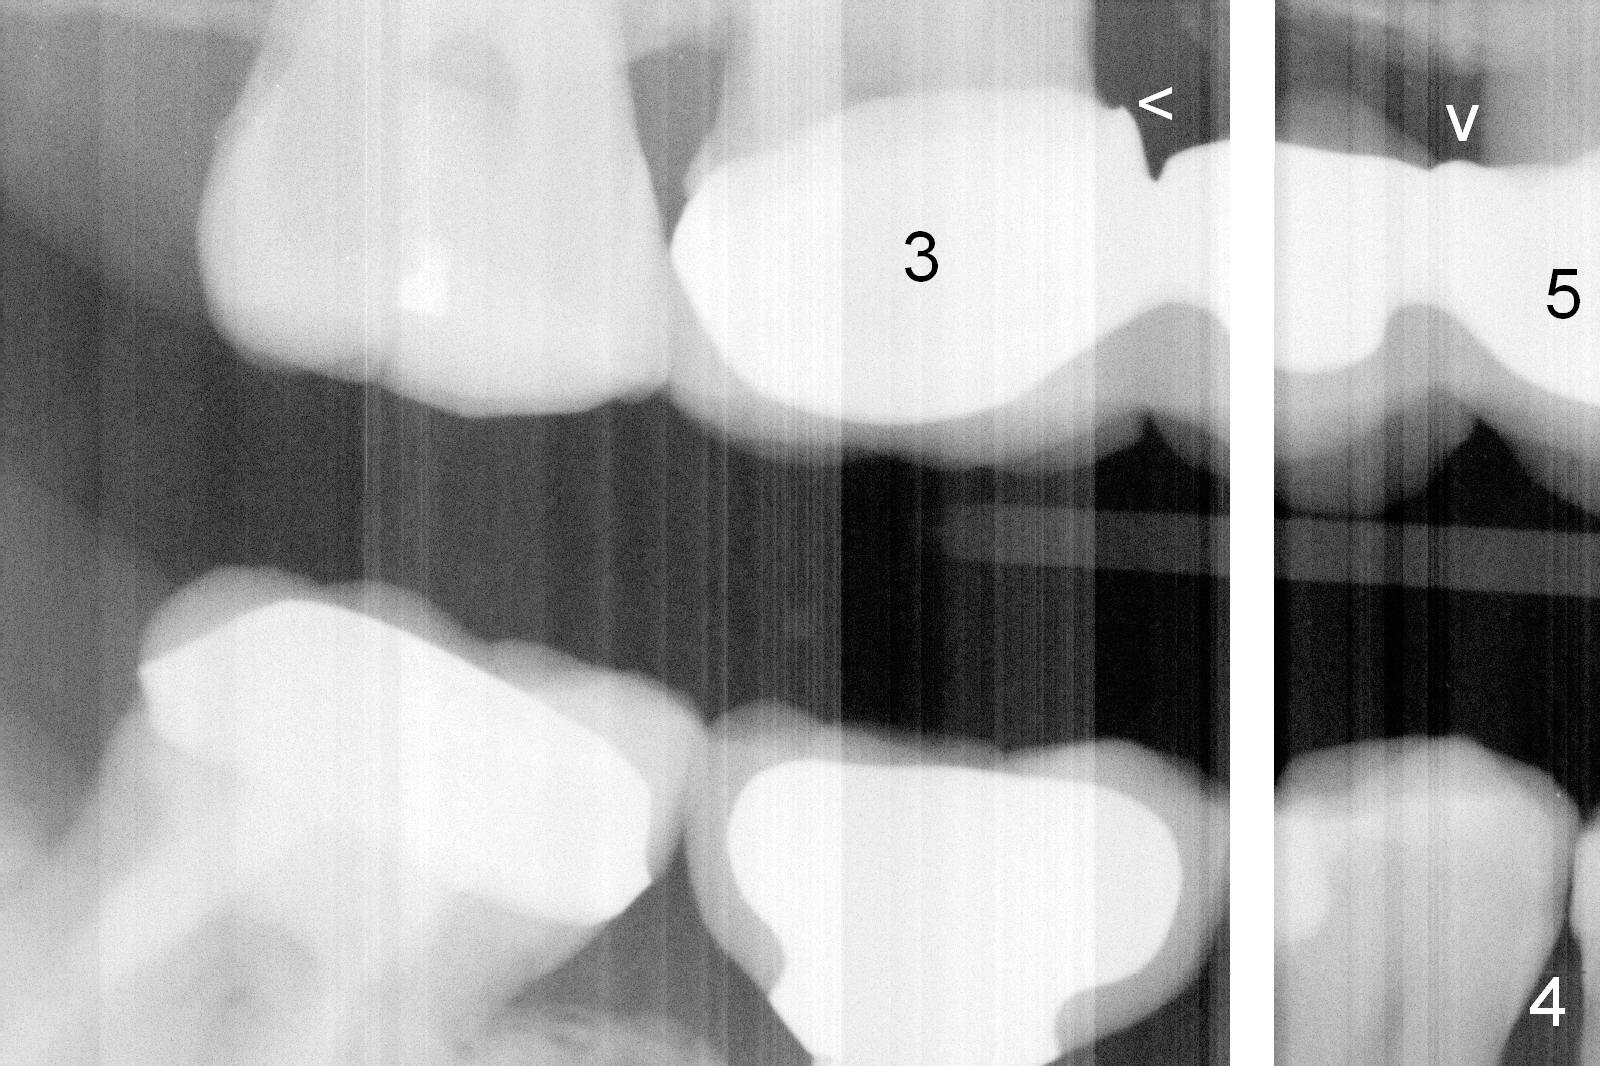

Ms. Li, a 34-year-old lady, had the upper right fixed partial denture made by an unlicensed dentist in California 10 years ago (Fig.1: #3-5). The gingival margin palatal to the retainers is erythematous (Fig.1 arrows). The patient's chief complaint is gum bleeding. The retainer at #3 is over-contoured buccopalatally (Fig.1, as compared to #14 in Fig.2), while the one at #5 is over-contoured buccopalatally and mesiodistally (compare to #12 in Fig.2). Panoramic X-ray (Fig.3), bitewing (Fig.4) and periapical film (Fig.5) all confirm that the bridge is over-contoured and that the retainers #3 and 5 have open margin (Fig.4 arrowheads). To improve oral hygiene and save the abutment teeth #3 and 5, it is in the patient's best interest to remove the bridge, place an implant at #4 and fabricate single-unit crowns at #3 and 5. Three to four months later, pyogenic granuloma develops between #4 and 5 (Fig.6 *) with generalized gingival erythema apically. The pontic at #4 and the retainer at #5 are to be removed first. An implant will be placed at #4 (Fig.7) with conjoined provisional at #4 and 5. The initial depth of osteotomy is 13 mm with Sinus Master Kit.